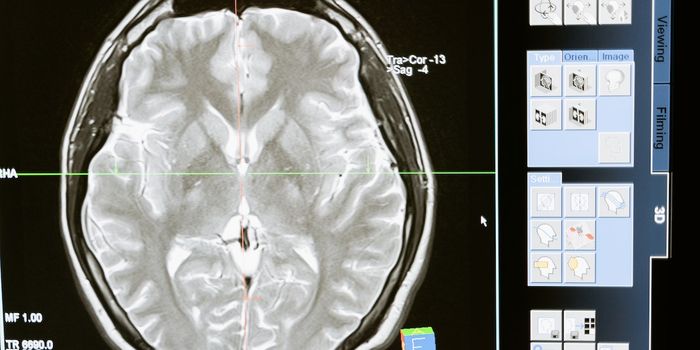

SEP 09, 2024NeuroscienceAlzheimer's patients with high levels of tau and amyloid-beta experience faster cognitive decline.

SEP 02, 2024NeuroscienceType 2 diabetes and prediabetes are linked to faster brain aging. Healthy lifestyle habits may protect against this effe ...

JUL 29, 2024NeuroscienceA blood test can detect Alzheimer's disease (AD) more accurately than traditional diagnostic methods.

JUL 15, 2024NeuroscienceA new AI tool that predicts Alzheimer's disease progression with 82% accuracy from routinely collected cognitive tests a ...